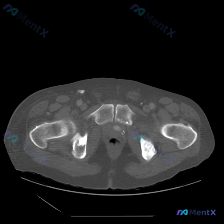

但拿到手的图像资料是:骨盆CT横断面(骨窗)。

我们先只盯着这张图说话,骨窗下的骨盆结构很清楚:

- 骨盆环与髋关节对位:双侧坐骨支、耻骨支、髋臼的骨皮质都是连续的,没有骨折线,股骨头和髋臼对位也很好。

- 明确的退行性改变:

- 双侧髋关节边缘有明显骨赘(骨质增生),负重区软骨下骨板硬化增厚,关节面不太平整,关节间隙看起来也有点窄;

- 耻骨联合处骨质硬化明显,边缘粗糙,还有散在的高密度钙化/骨赘,周围软组织在这个窗位下没看到明显肿胀或肿物。

所以,基于这张骨窗图像,唯一可以确定的诊断是:双侧髋关节及耻骨联合退行性骨关节病。